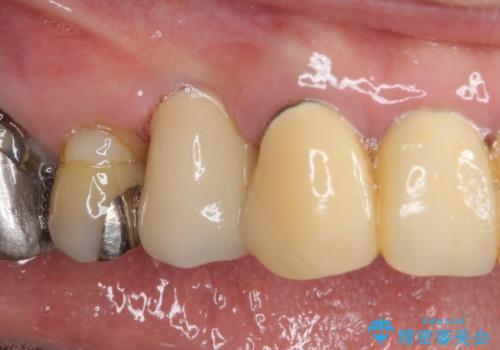

小臼歯の審美治療 ストローマンインプラントとカスタムアバットメント

- 60代女性

- 10ヶ月

- 5-10回

- 治療費の目安: 60万円費用は治療当時の料金となります